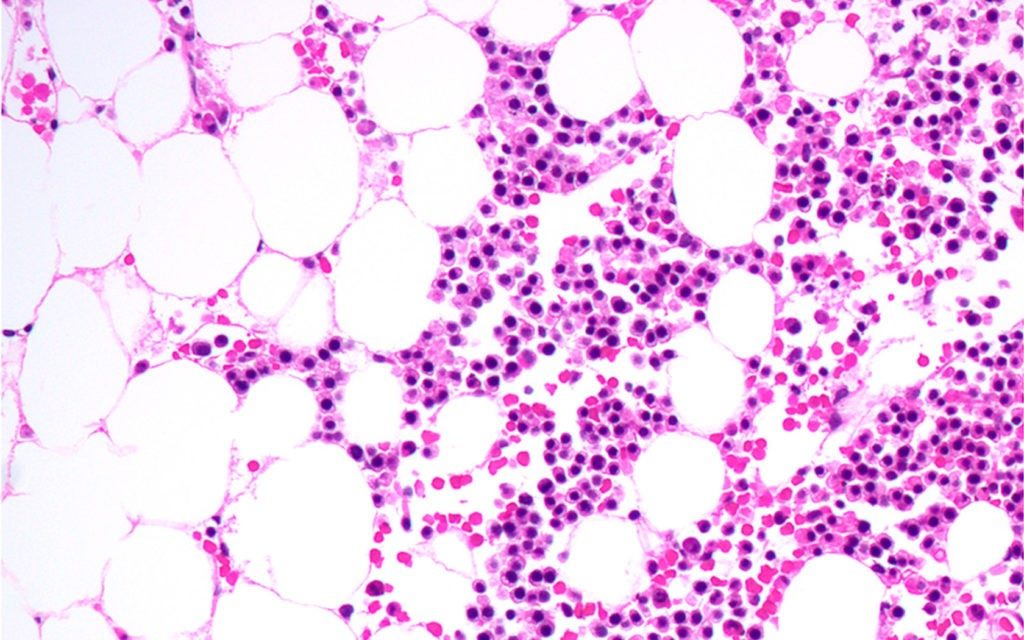

Initial findings from a multi-national open-label phase Ib study of inhibitory drug therapy for relapsed or refractory acute myeloid leukemia (AML) have demonstrated a complete response in up to 50 percent patients say researchers at The University of Texas MD Anderson Cancer Center .

The patients, age 60 years or older, received therapy with venetoclax in combination with cobimetinib or idasanutlin. The clinical trial followed...